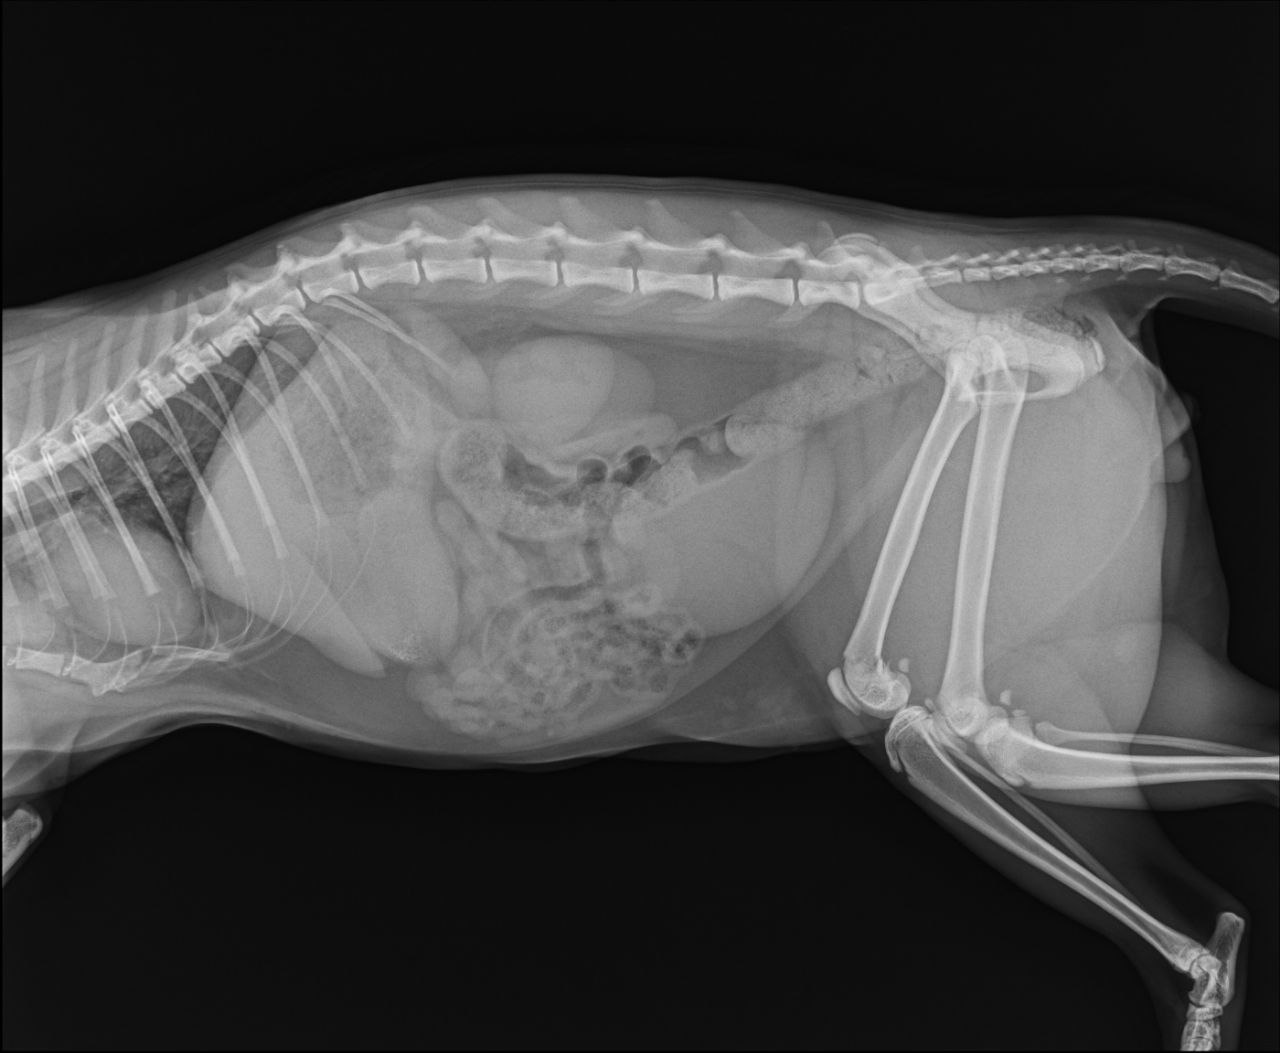

Перелом бедренной кости, требуется операция. В остальном здоров и бодр, ест, пьёт, ходит в туалет.

Тут закрытый перелом не кости а коленного сустава, сильно выраженная бронхиальная картина. Антибиотик нужен

Он писает? На снимке мочевой как дыня переполнен